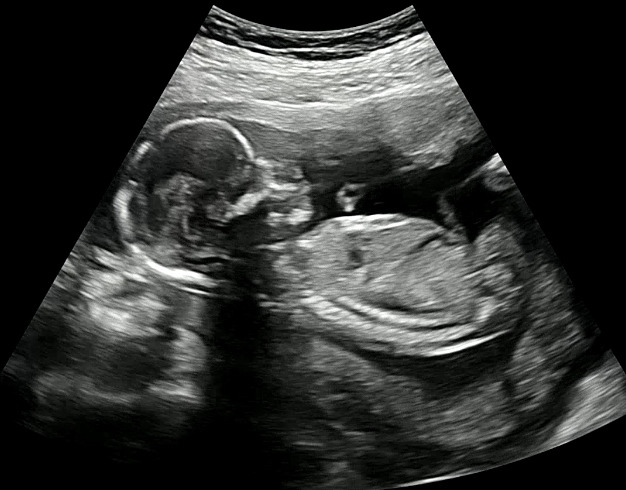

글을 올리지 못했던 두 달여간 나에게 많은 일들이 있었다. 그중 가장 중요한 일은 내가 다시 둘이 되었다는 것. 나의 뱃속에 현재 17주가 된 둘째가 있다. 드디어 임신 중기에 들어섰고, 임신 초기동안 입덧으로 힘들어 글을 쓰는 행위에 도무지 집중을 하지 못했다. 글쓰기는커녕, 글을 읽을 수도 없었다. 공복일 때나, 식사를 한 후에도 속은 계속 울렁거렸고 구토를 할 듯한 느낌이 끊임없이 나를 괴롭혔다. 쏟아지는 잠은 말할 것도 없고.

엄마 뱃속에서 건강하게 자라고 있길 바라는 우리 둘째. 지금도 뱃속에서 뽀롱뽀롱 움직이는 게 느껴지는 요즘. 널 만날 그 순간이 무척이나 설레고 기다려진다. 빨리 보고 싶은 마음을 애써 참으며 너를 궁금해하는 하루, 하루가 차곡차곡 쌓여간다.